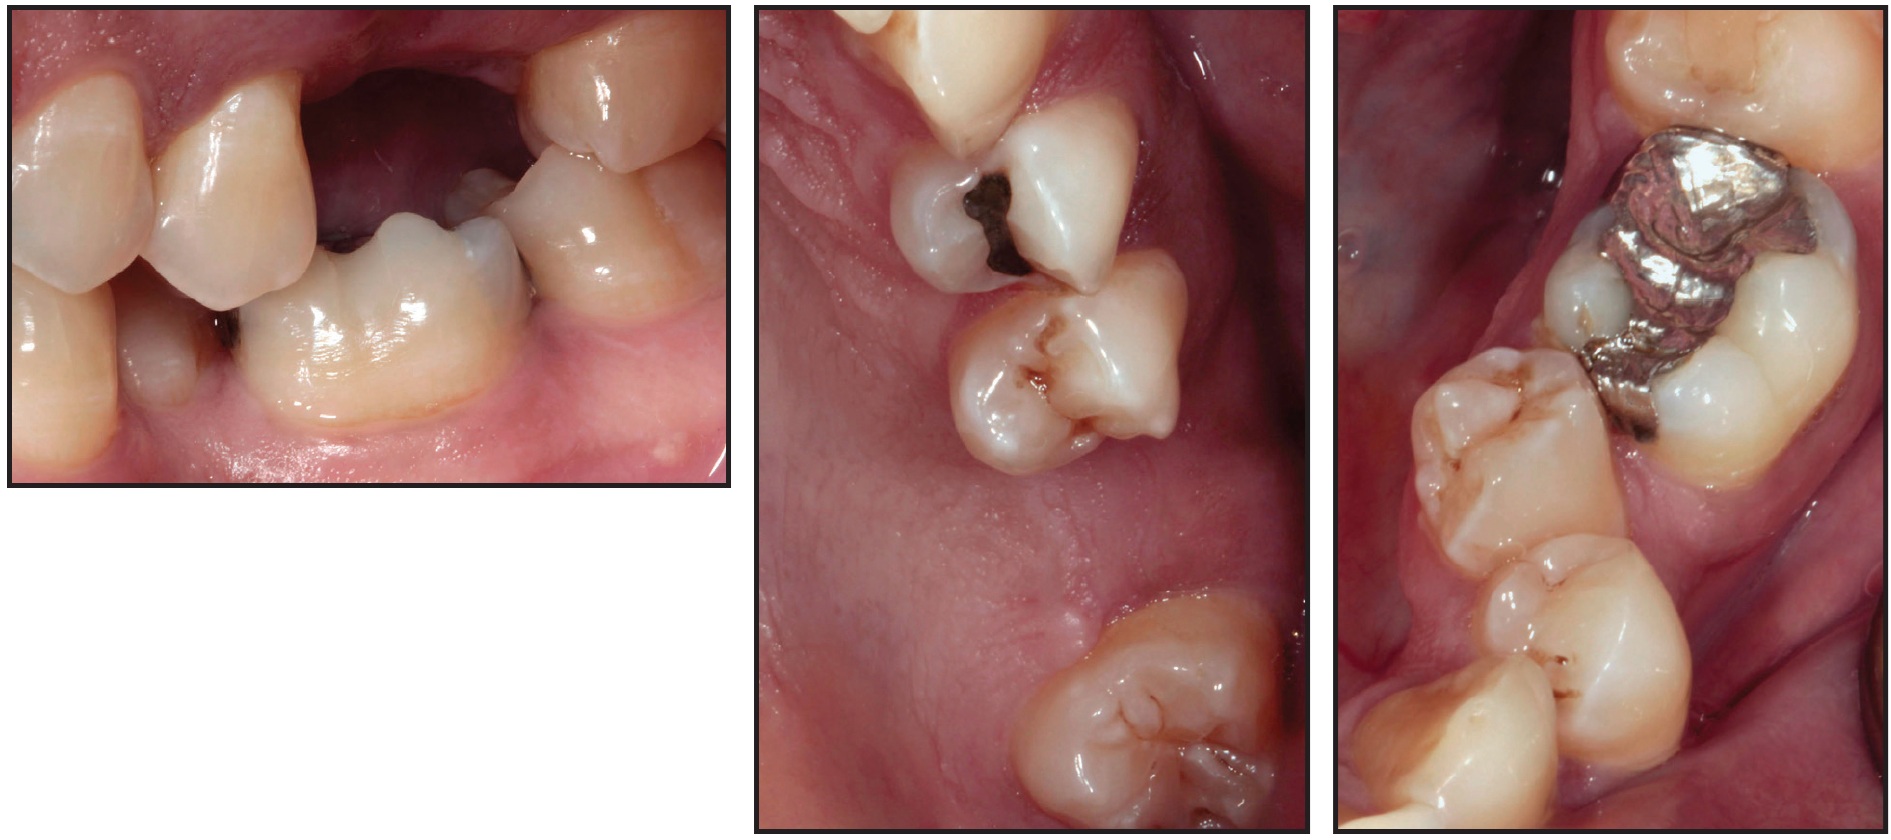

A second technique is demonstrated in a 30-year-old male who presented with a missing lower right first molar and an unrestored implant that had been placed 10-15 years previously. The lower right second molar had drifted mesially into the first-molar space and was leaning into the abutment of the implant (Fig. 4). The remaining dentition was in a Class I occlusal relationship.

Fig. 4 Case 2. 30-year-old Class I male patient with mesially inclined lower right second molar leaning into implant in first-molar space.